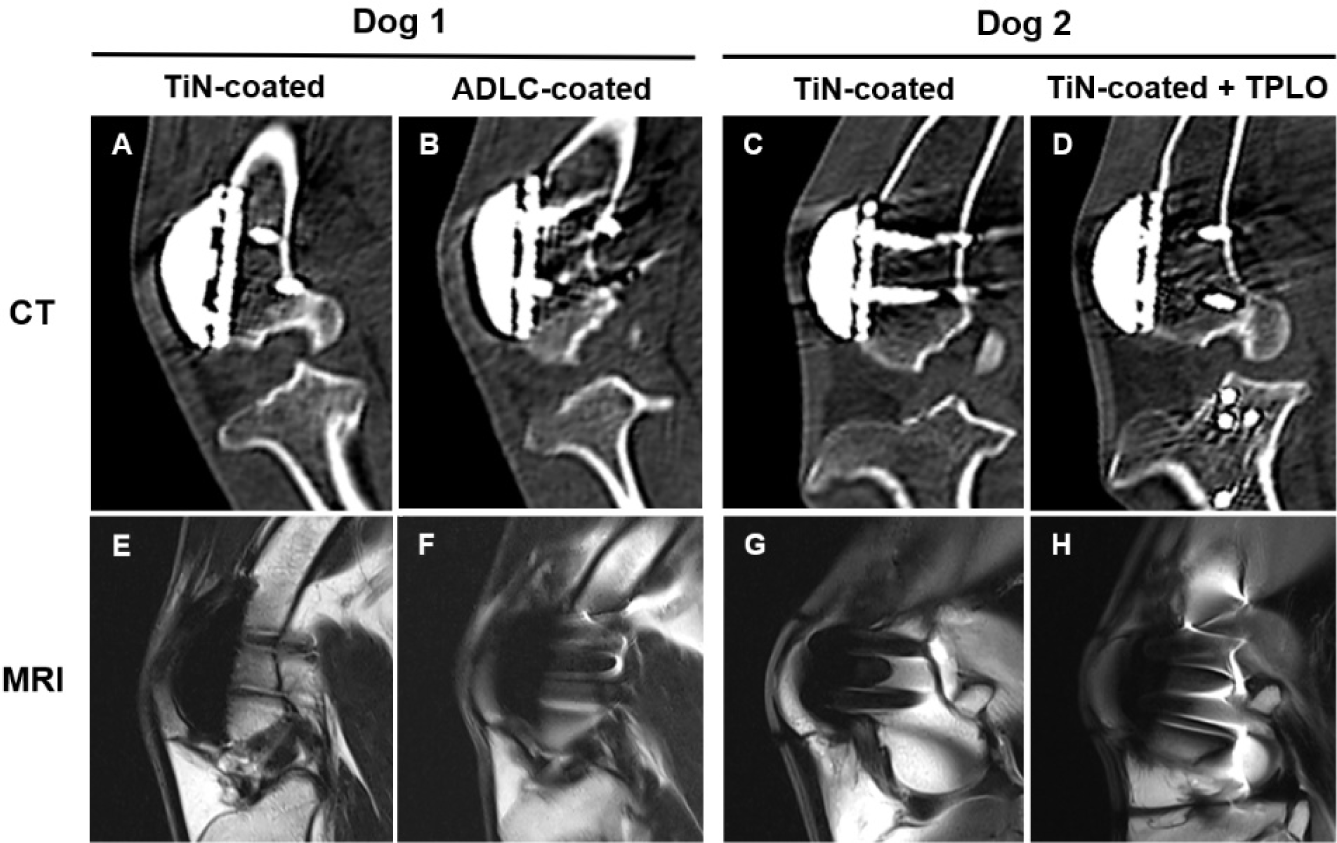

To enable comparative evaluation, Dog 1 received a TiN-coated prototype in the right stifle and a clinically available ADLC-coated device in the left stifle. Dog 2 received bilateral TiN-coated implants, and a tibial plateau leveling osteotomy (TPLO) was additionally performed on the left stifle to simulate complex orthopedic conditions.

Fluoroscopic images were obtained immediately after surgery, at 1, 2, 4, and 8 weeks, and at 6 and 12 months using a flat-panel detector C-arm system (OSCAR Prime, GENORAY, Seoul, Korea; 60 kVp, 1.6 mA, pulse mode 8 frames/s). Computed tomography (CT) scans were performed at 8 weeks, 6 months, and 1 year under general anesthesia (Incisive CT, Philips, Amsterdam, Netherlands; 140 kVp, 100 mAs). At 1 year, magnetic resonance imaging (MRI; 3.0 T, Achieva, Philips Healthcare, Best, The Netherlands) was performed using a T2-weighted fast spin-echo sequence (TR 3,000 ms; TE 100 ms; slice thickness 3.0 mm) with a dedicated stifle coil to evaluate patellofemoral alignment and periarticular soft tissues.

Fluoroscopic images obtained immediately after implantation revealed minor gaps at the bone–implant interface, which resolved by week 8, confirming stable fixation. At 6 months and 1 year, no implant loosening, bone resorption, or pathological changes were detected (Fig. 5). CT and MRI analyses at 8 weeks, 6 months, and 1 year confirmed proper patellofemoral alignment and smooth articulation between the artificial groove and patella. MRI at 1 year demonstrated intact quadriceps and patellar tendons, no joint effusion, and no abnormal synovial proliferation (Fig. 6). These imaging findings verify long-term implant stability, accurate alignment, and soft-tissue compatibility.

Preclinical evaluation in beagles demonstrated successful implantation, stable fixation, and restoration of normal gait within weeks postoperatively. Radiographic and advanced imaging analyses (CT, MRI, and micro-CT) confirmed proper patellofemoral alignment, satisfactory bone–implant integration, and intact surrounding soft tissues without pathological findings. These findings are consistent with recent imaging-based methods for evaluating bone–implant integration [32–34]. Although clinical lameness grading and multimodal imaging were sufficient for confirming functional recovery in this feasibility study, objective gait analysis such as quantitative weight-bearing assessment was not performed; incorporating kinetic measurements will strengthen future evaluations. In Dog 2, TiN-coated implants were intentionally combined with TPLO to evaluate performance under a more complex surgical condition. Although an ADLC+TPLO group would have provided an additional comparator, ADLC-coated implants are already clinically established with well-documented safety, and the present study prioritized assessing the newer TiN system under both standard and combined procedures. Collectively, these results indicate that the TiN-coated PGR system shows clinical outcomes comparable to those of the ADLC-coated device while offering manufacturing and cost advantages that may enhance accessibility for general veterinary practice.